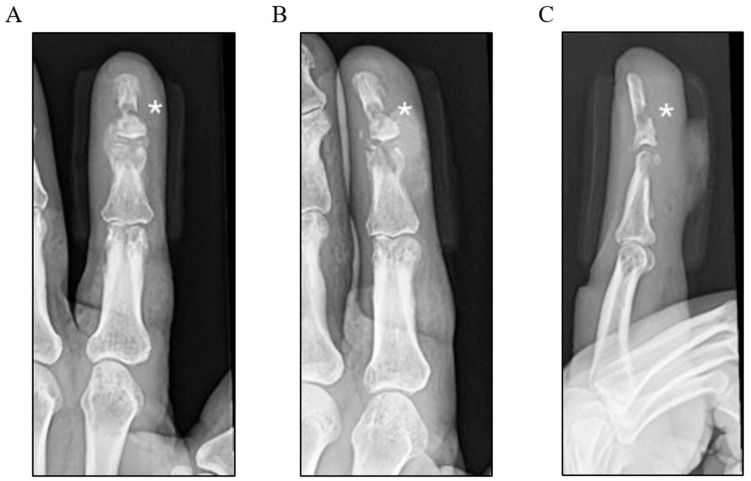

犬Schaalia是一种革兰氏阳性,兼性厌氧,棒状细菌,最初从狗的粘膜和皮肤中分离出来。虽然它是正常犬口腔菌群的一部分,但它很少与人类疾病有关,只有一个先前的蜂窝织炎病例报告了狗咬伤。病例介绍:我们提出的情况下,一个57岁的免疫功能正常的人谁发展了骨髓炎的左食指后延迟呈现后,狗咬。尽管最初使用经验性口服抗生素进行保守治疗,但感染仍在进展,最终需要手术清创并在近端指间关节处终止手指。术中骨标本的培养产生犬沙利亚菌的生长,在扩展培养中未发现其他病原生物。结论:这是首例记录在案的人类沙利亚犬相关骨髓炎病例,也是首例需要手术干预的病例,扩大了该生物已知的临床范围。该病例强调了延迟干预多微生物动物咬伤的风险,并突出了沙利亚种作为机会性人畜共患病原体的新作用,特别是在深部难治性感染的情况下。

Schaalia canis is a Gram-positive, facultatively anaerobic, rod-shaped bacterium originally isolated from the mucosa and skin of dogs. While it is a part of the normal canine oral flora, it has rarely been implicated in human disease, with only one prior case of cellulitis reported following a dog bite. Case Presentation: We present the case of a 57-year-old immunocompetent man who developed osteomyelitis of the left index finger following a delayed presentation after a dog bite. Despite initial conservative management with empirical oral antibiotics, the infection progressed, eventually requiring surgical debridement and the terminalisation of the finger at the proximal interphalangeal joint. Cultures from intraoperative bone specimens yielded the growth of Schaalia canis, with no other pathogenic organisms identified on the extended culture. Conclusions: This is the first documented case of Schaalia canis-associated osteomyelitis in a human and the first to necessitate a surgical intervention, expanding the known clinical spectrum of this organism. This case underscores the risks of delayed intervention in polymicrobial animal bite wounds and highlights the emerging role of Schaalia species as opportunistic zoonotic pathogens, particularly in the setting of deep, refractory infections.